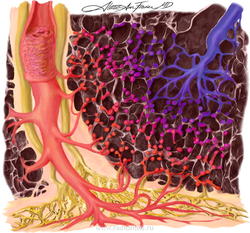

Легочный капиллярный гемангиоматоз